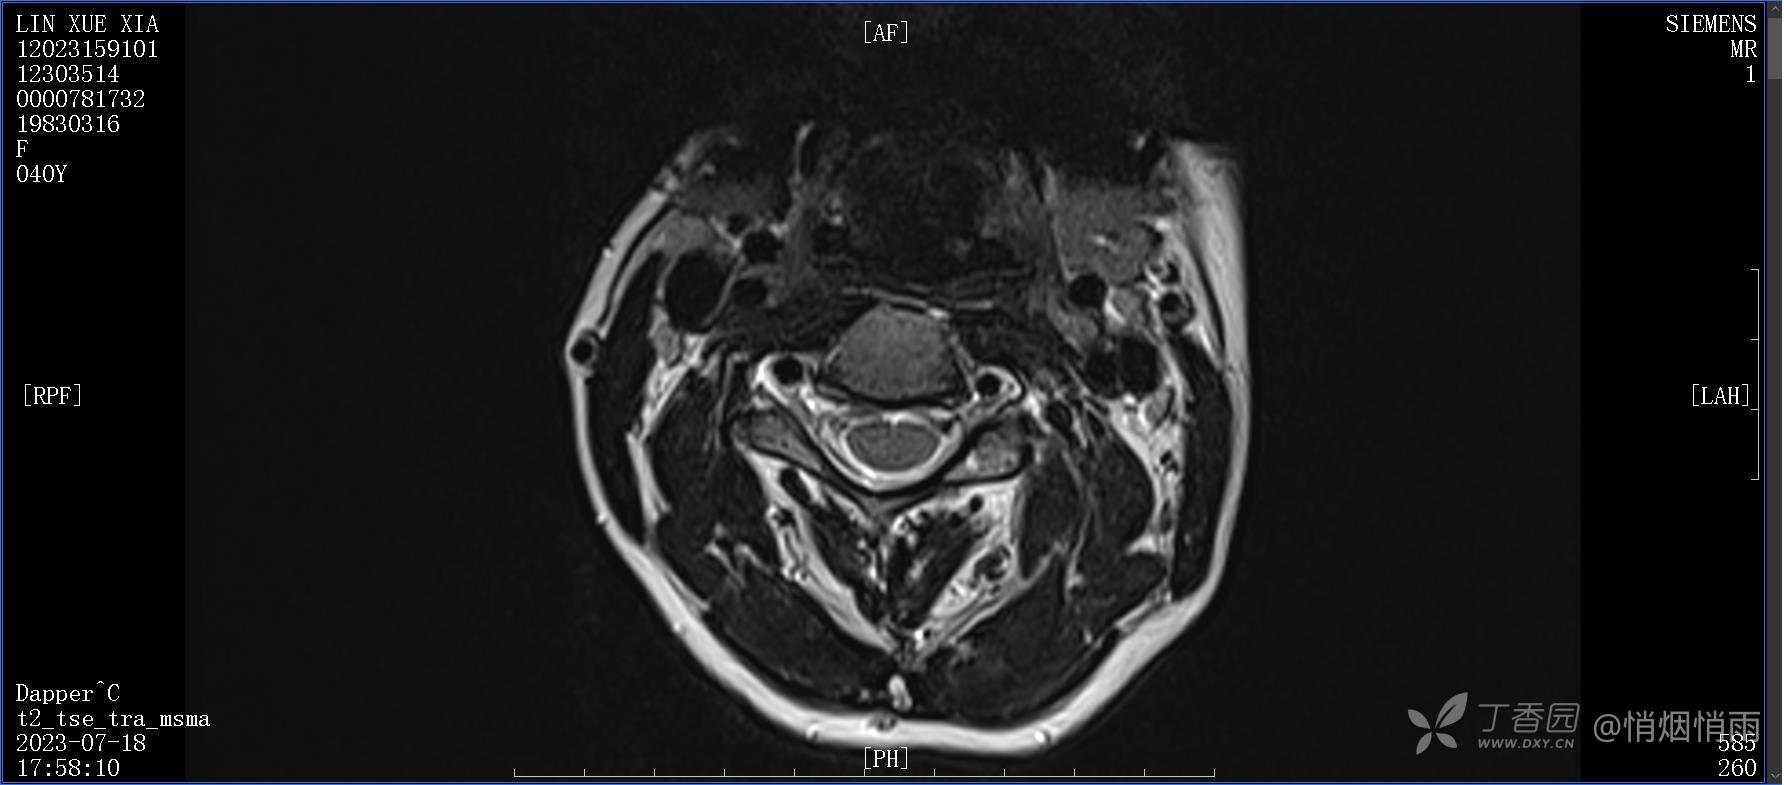

NeurothinkerZ 推荐患者女性,40岁,因右肩背部疼痛班活动受限4日余入院(2023-07-17)。

病史:入院前4天无明显诱因突然感右肩背疼痛伴随活动受限,自行口服依托考昔、艾瑞昔布等药物治疗,院外应用肩关节局部手法按摩等,均无明显改善。外院门诊诊为颈椎病。自诉既往多次“胸椎小关节紊乱”于当地诊所行手法按摩,治疗后好转,否认慢性疾病病史、外伤史、手术史,诉青霉素过敏,无其他药物食物过敏史,否认吸烟史、饮酒史,月经正常,经量正常。

目前的诊断,暂时依据辅助检查诊为肩袖损伤,但是患者疼痛的性质和特点,却不是单纯的肩袖损伤所致。考虑过胸廓出口综合征,但是该疾病会出现肩胛区的疼痛吗?(由于考虑到费用的问题,没再进行下一步的检查)带状疱疹会有如此的症状吗?